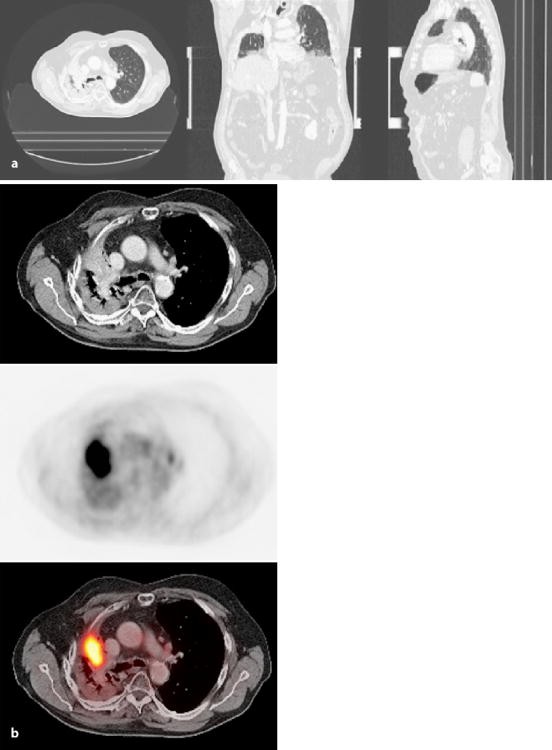

Abb 2 8 Fdg Pet Ct Bei Einem Patient Mit Bronchialkarzinom Links Download Scientific Diagram